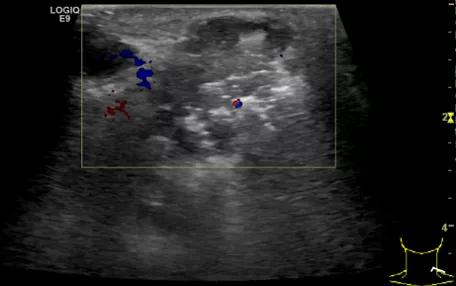

第5例是乳腺癌的患者,右乳恶性肿瘤术后化疗后1年出现淋巴结转移,患者基本情况差,拒绝放化疗,行局部热消融后也实现充盈缺损,术后一个月强化信号消失。

(病例5图例)